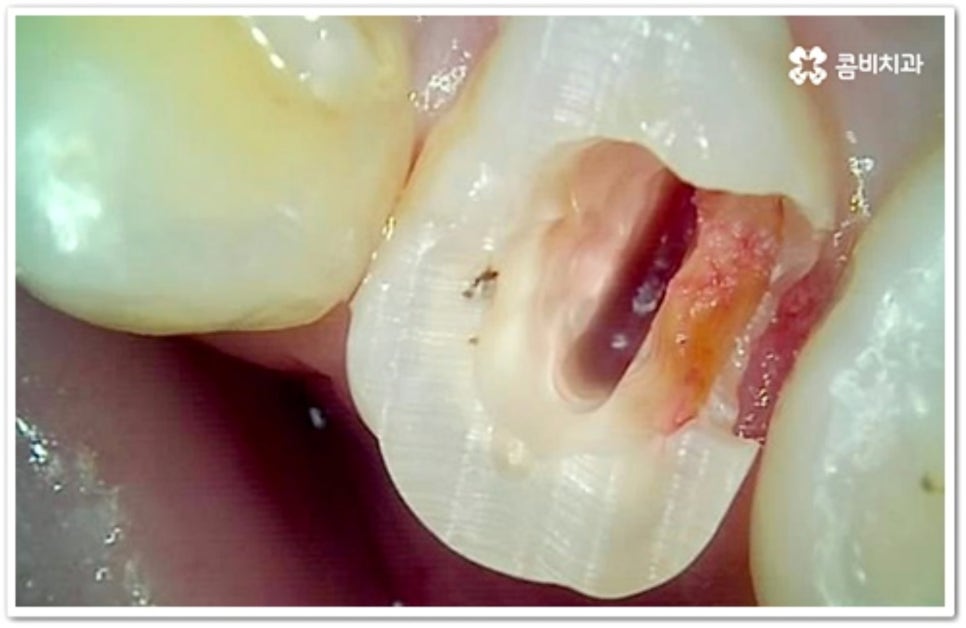

인접면에 충치가 생겼을 때 치료 과정은 손상 정도에 따라 달라질 수 있는데 만약 아주 경미하다면 바로 레진으로 이를 수복할 수 있겠지만 치아 경계면이 무너졌다면 직접적인 레진 수복으로는 생리학적 형태를 재현하기 까다롭기 때문에 본을 떠서 외부에서 금이나 세라믹 보철물을 만들어 끼워넣는 간접적인 방법을 통해 도움을 받을 수 있어요. 환자분들의 상황에 따라 치아 일부만 수복해야 할 때는 인레이 치료를 하고 손상이 크면 신경치료를 한 후 필요시 내부에 기둥을 세우고 치아 전체를 다듬어 씌우는 크라운 치료를 이용하게 될 거예요.

신경치료를 통해 감염된 부분을 모두 드러내야 한다면 이미 병증이 많이 진행되었다는 의미이기 때문에 치료 시간과 비용 부담이 늘어나고 예후도 그리 좋지 않을 수 있어요. 그럼에도 불구하고 자연 치아를 살릴 수 있다면 가능한 한 수명을 늘리는 방향으로 보존 치료를 해 주는 것이 좋으니 구강 건강을 위해 치료 시기를 더 늦추지 않도록 주의하시길 권유드리고 있습니다.